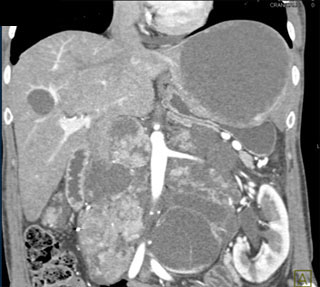

The best diagnosis in this case is?

lymphoma

germ cell tumor

metastatic renal cell carcinoma

disseminated TB